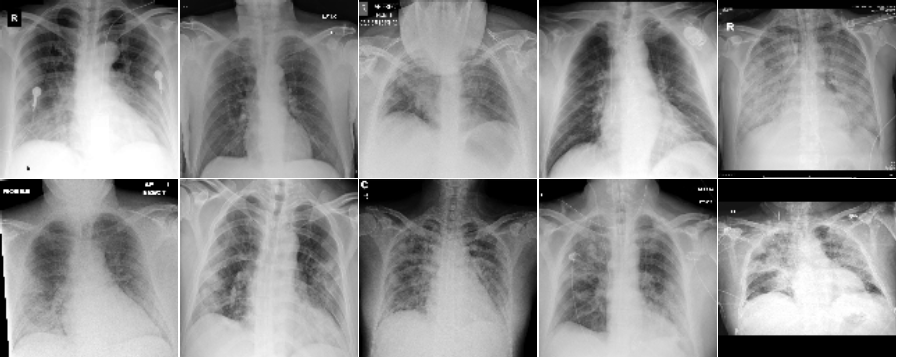

This section presents visualization of the proposed architecture. These visualizations are presented in Figure 5. Unlike Figure 2 that is an executive summary with each position representing many samples, these visualizations in Figure 5 are sample-wise plots. In other words, the 10 original images that are sized 128 by 128 in Panel A and Panel B are the same samples in the second row, 1st Conv. Layer, and the third row, 2nd Conv. Layer.

Visualization Interpretation The plot in Figure 5 of the original images for COVID-19 patients has grey and cloudy textures in chest area. Because an X-ray picture is at its brightest when most of the light beams emitted are bounced back from the object, we can observe bones to be the color “white” while the margin to be completely “black”. For muscle and organs inside human body, X-ray beams that are emitted can only partially be collected and this causes the greyscale on the X-ray images in chest area. For COVID-19 patients, there are grey and shaded area in the chest X-ray pictures. This is due to the inflammatory fluid when patients exhibit pneumonia-like symptoms. The fluid inside chest area is a consequence of human immune system fighting against outside diseases. This shaded (as seen in Panel A of Figure 5) prevents us from observing the clear location of lungs. This is different in Panel B where the lung areas are dark and almost black, because a healthy lung is filled with air (i.e. normal cases and X-ray image presents color black). The black and white contrast in the two panels is directly related to how much inflammatory fluid there is in human lungs. This contrast translates to greyscale on pictures and it is directly related with COVID cases and non-COVID cases (i.e. response variable ). The same contrast can be seen using the new variables (these are ’s based on equation 4) in the 1st Conv. Layer (sized 61 by 61). For COVID-19 patients, the lung area is cloudy and unclear while the healthy cases it is clearly visible. This is not a surprising coincidence because the proposed new variable modules, ’s, are engineered using equation 4 which relies on the response variable in training set. The images sized 61 by 61 from the proposed algorithm is a direct translation of not only the original pixels but also response variable. In other words, this visualization presents how I-score sees image data.

| Panel A: | Panel B | |

| True Label: COVID | True Label: Non-COVID | |

| Input Images: 128 by 128 | Input Images: 128 by 128 | |

| (Randomly select 10 samples) | (Randomly select 10 samples) | |

| Row (a) |  |

|

| 1st Conv. Layer: 61 by 61 | 1st Conv. Layer: 61 by 61 | |

| (Starting Point = 6, Window 2 by 2, Stride = 2) | (Starting Point = 6, Window 2 by 2, Stride = 2) | |

| Remark: variables | Remark: variables | |

| Same 10 images above with 3,721 variables | Same 10 images above with 3,721 variables | |

| Labels predicted using Model 1 | Labels predicted using Model 1 | |

| Row (b) |  |

|

Discussion for Figure 5.

This figure presents visualization summary for 10 randomly sampled images from COVID class and non-COVID class (each has 10). Panel A is for COVID patients and Panel B is non-COVID people. The first row plots the original images that are sized 128 by 128. The 1st Conv. Layer generates new variables. We plot the same 10 images from both classes using these 3,721 variables in the second row. We also print the predicted COVID probabilities on top left corner of each image. The 2nd Conv. Layer generate variables. We plot the same 10 image samples from both classes using these 900 variables in the third row. We also print the predicted COVID probabilities on top left corner of each image assuming using only these 900 variables as predictors. The plot of the original images for COVID-19 patients has grey and cloudy textures in chest area. This is due to inflammatory fluid when patients exhibit pneumonia-like symptoms. This shaded (as seen in Panel A) prevents us from observing the clear location of lungs. This is different in Panel B where the lung areas are dark and almost black which means the lung is filled with air (i.e. normal cases). The black white contrast in the two panels is directly related to how much inflammatory fluid there is in human lungs which translate to greyscale on pictures. The same contrast can be seen using the new variables (these are ’s based on equation 4) in the 1st Conv. Layer (sized 61 by 61). For COVID-19 patients, the lung area is cloudy and unclear while the healthy cases it is clearly visible.

|

Discussion for Figure 5.

Original Images to 1st Conv. Layer. The input images are sized 128 by 128. With the 1st Conv. Layer constructed, we have new variables. We trace back to the same samples as shown in the first row of Figure 5 and use these 3,721 variables only. When we plot these samples with these new variables, we resize them back in matrix form of 61 by 61. Panel A is for COVID class and Panel B is for non-COVID class. In addition, we use Model 1 in Table 4 to produce the texts that states predicted probability of COVID class. The red color implies ground truth to be COVID class (Panel A) and the green color implies ground truth to be non-COVID class (Panel B).

1st Conv. Layer. to 2nd Conv. Layer. From the resulting matrix of the 1st Conv. Layer, we are left with 3,721 variables. We go through the proposed design in Table 4 and we create a new convolutional layer, i.e. 2nd Conv. Layer. This new layer has variables. We take the same 10 sampled images from before and we use these 900 variables to present these images. In this presentation, we resize these 900 variables into shape 30 by 30. In other words, we get a smaller matrix that we can plot that exhibit mini version of similar patterns as before. We use Model 4 to generated the predicted probabilities. These probabilities are printed on the top left corner of each image and they are color coded similarly as before (red probabilities have ground truth of COVID class while green probabilities have ground truth of non-COVID class).